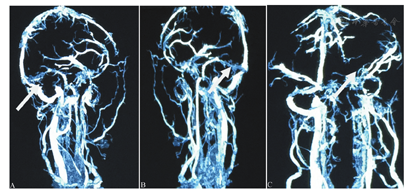

诊疗经过:入院当天MRV示左侧颈内静脉、侧窦显影不良,考虑先天发育,直窦未见显影(图2)。6月4日全身麻醉下行DSA,提示双侧大脑内静脉、大脑大静脉、Galen静脉和直窦静脉血栓。给予尿激酶(50万U)静脉接触溶栓及机械取栓,上述血管部分显影(图3)。术后予甘露醇(125 ml,1次/4 h)积极脱水降颅压和低分子肝素钠(克赛;0.4 ml,1次/12 h)皮下注射抗凝治疗。次日凌晨患者出现双侧瞳孔不等大,复查头颅CT提示双侧基底节、双侧丘脑多发异常信号,大脑大静脉池高密度,梗阻性脑积水伴间质性脑水肿(图4A),考虑脑疝形成。予紧急脑室穿刺引流,脑疝不能完全逆转。当日在全身麻醉下行双侧额颞顶部开颅去骨瓣减压,术中颅内压高,同时行双侧颞极清除内减压术。术后复查头颅CT显示颅骨去骨瓣减压术后改变,右侧基底节区脑出血破入右侧侧脑室,脑内多发异常密度,静脉性梗死可能(图4B)。术后(6月9日)复查头颅CTV示:直窦、左侧横窦纤细显影,下矢状窦、大脑内静脉及大脑大静脉显影浅淡,左侧乙状窦、颈静脉较对侧血管细(图5)。

A:左侧颈内静脉、侧窦显影不良,考虑先天发育(白色箭头);B:直窦未见显影(白色箭头)

A:直窦、大脑内静脉和Galen静脉未见显影;B:介入治疗过程;C:术后直窦浅淡显影,Galen静脉显影(白色箭头)